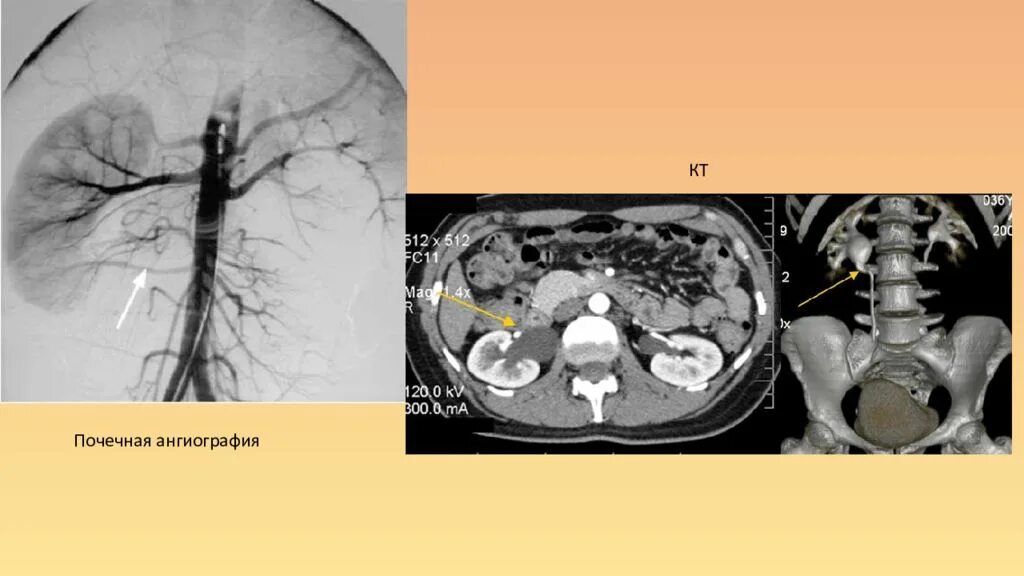

Гидронефроз почки после операции